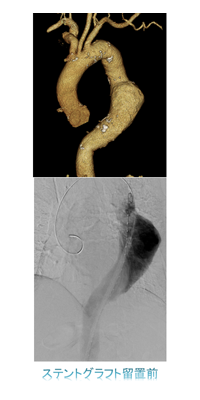

ハイブリット手術室では経皮的大動脈弁置換術(TAVI)、経皮的僧帽弁クリップ術(MitraClip)、左心耳閉鎖術(WATCHMAN)などの構造的心疾患(SHD:Structure Heart Disease)に対するインターベンションをはじめ、大動脈解離や大動脈瘤に対するステントグラフト内挿術(TEVAR、EVAR)、エキシマレーザーを用いたデバイスリード抜去術など、様々な手技を行っています。